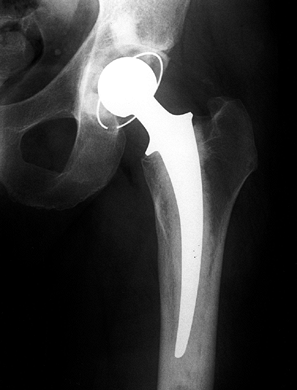

Using the proximal pin as a handle, rotate the femoral head anteriorly (Fig. 125.22 and Fig. 125.23). In the case of

P.3284

posterior rotation, place a Steinmann pin in the superolateral corner

of the proximal fragment from anterior to posterior. The second K-wire

serves as a reference point for measurement of the angle of rotation.

Figure 125.22. Schematic of the Sugioka transtrochanteric rotational osteotomy of the femoral head. (Courtesy of Professor Y. Sugioka.)

Figure 125.23.

Transposition of necrotic focus of femoral head anteroinferiorly away

from weight-bearing area as a result of anterior rotation of the

femoral head. (A) before rotation and (B)

after rotation. (From Sugioka Y, Mohtai M. Osteonecrosis of the Femoral

Head: A Conservative Surgical Solution. In: Sedel L, Cabanela M, eds. Hip Surgery: Materials and Developments. London: Martin Dunitz, 1998, with permission.) -